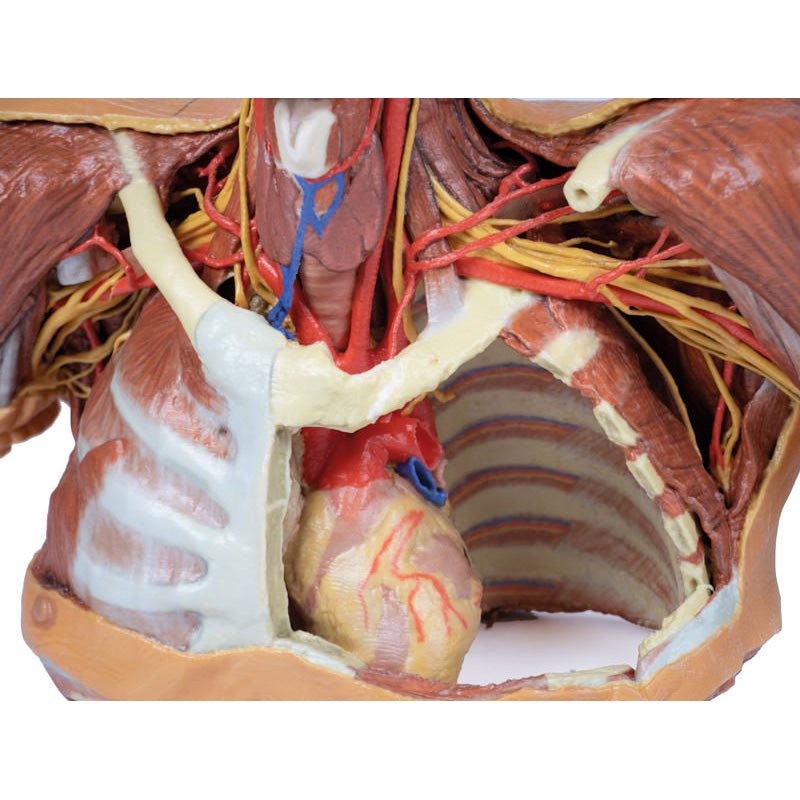

Thorax:

The thorax has been opened via a ‘window’ on the left to display the internal thoracic wall and mediastinum. The left lung has been removed and the intercostal spaces are discernable deep to the parietal pleura although intercostal neurovascular bundles are only discernable posteriorly. The pericardium has been removed to expose the heart with its apex pointing inferiorly, anteriorly, and to the left. The left side of the heart is exposed as are the left pulmonary veins and arteries (above left main bronchus), ascending aorta, aortic arch and commencement of the descending thoracic aorta. The left vagus nerve and left recurrent laryngeal nerve are easily identified. The right half of the anterior and lateral thoracic wall are intact and display the muscles of the intercostal spaces and inserting hypaxial muscles from the right upper limb. If the specimen is viewed from below, the right lung and pleural spaces along with the diaphragmatic surface of the heart are all evident. While the skin and superficial fascia posterior thorax has been left intact, the distribution of cutaneous branches of dorsal rami have been illustrated along the left side of the specimen.

Thorax:

The thorax has been opened via a ‘window’ on the left to display the internal thoracic wall and mediastinum. The left lung has been removed and the intercostal spaces are discernable deep to the parietal pleura although intercostal neurovascular bundles are only discernable posteriorly. The pericardium has been removed to expose the heart with its apex pointing inferiorly, anteriorly, and to the left. The left side of the heart is exposed as are the left pulmonary veins and arteries (above left main bronchus), ascending aorta, aortic arch and commencement of the descending thoracic aorta. The left vagus nerve and left recurrent laryngeal nerve are easily identified. The right half of the anterior and lateral thoracic wall are intact and display the muscles of the intercostal spaces and inserting hypaxial muscles from the right upper limb. If the specimen is viewed from below, the right lung and pleural spaces along with the diaphragmatic surface of the heart are all evident. While the skin and superficial fascia posterior thorax has been left intact, the distribution of cutaneous branches of dorsal rami have been illustrated along the left side of the specimen.